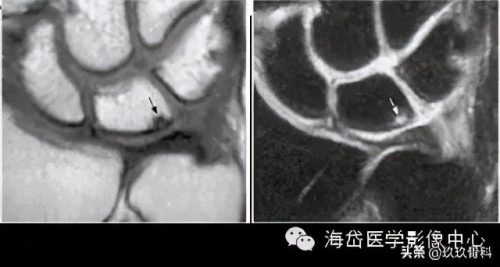

②MRI:MRI对骨髓变化敏感,在骨损伤早期就能反映出骨髓水肿性改变,可做到早期诊断。

随压迫时间延长MRI可见高信号(T2WI)逐渐增强,并形成透镜样改变,晚期形成“双线”或“双环”征。“双环”征提示坏死区内可能有新骨形成,“双线”征表明骨坏死区有瘢痕组织形成。

由于尺骨阴性、阳性变异引起的骨坏死是可逆的,当尺骨变异被纠正后骨坏死可以转化为正常骨结构。因此MRI除可用于早期诊断外还可作为有效的动态观察手段,当骨髓水肿性变化无减轻、消失,反而逐渐明显时,提示临床应早期解除桥联状态(主要是解除压迫),可有效防止月骨、三角骨坏死的发生或降低其发生率。